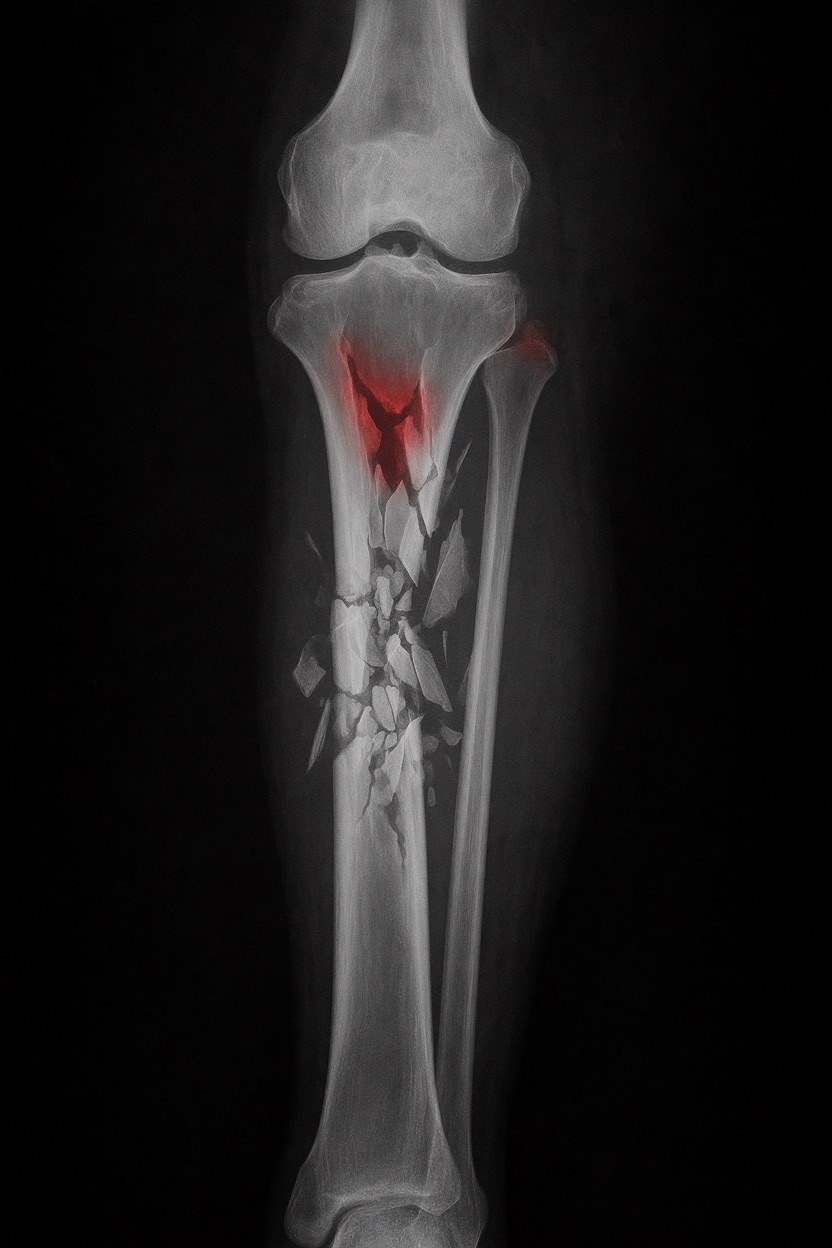

アートや写真の編集用に設計されたFlux Kontextのようなモデルを、医療画像、たとえば「単純な」骨折の赤色マーキングに使用できるか?

即答:面白い結果を出すが、過剰に反応し、医療ツールとしては信頼性に欠ける。これはアイデアを試すためのプロトタイプに過ぎない。

さらに攻撃的な設定(例:rk beta57、Denoise 1.0)では、**偽陽性100%、検出100%**という馬鹿げた結果に:すべてを赤で塗りつぶし、健常部もほぼすべて骨折と誤認する。未経験の目には区別がつかない。

Civitai用に作成した、100% AI生成の合成ミニデータセット(健康なX線10枚、骨折のあるX線10枚)でテスト:

- 健康な骨での偽陽性:100%

- 骨折検出:≈ 45%